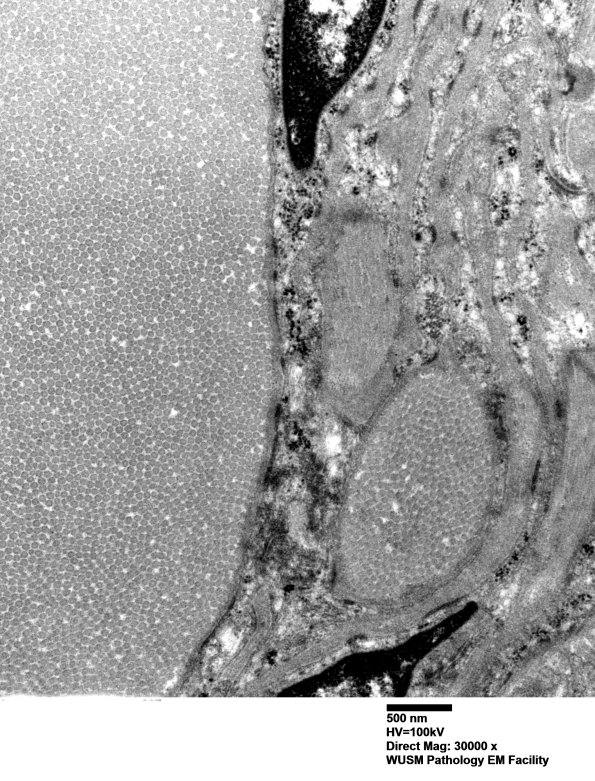

Close up image of large collections of collagen (electron micrograph)